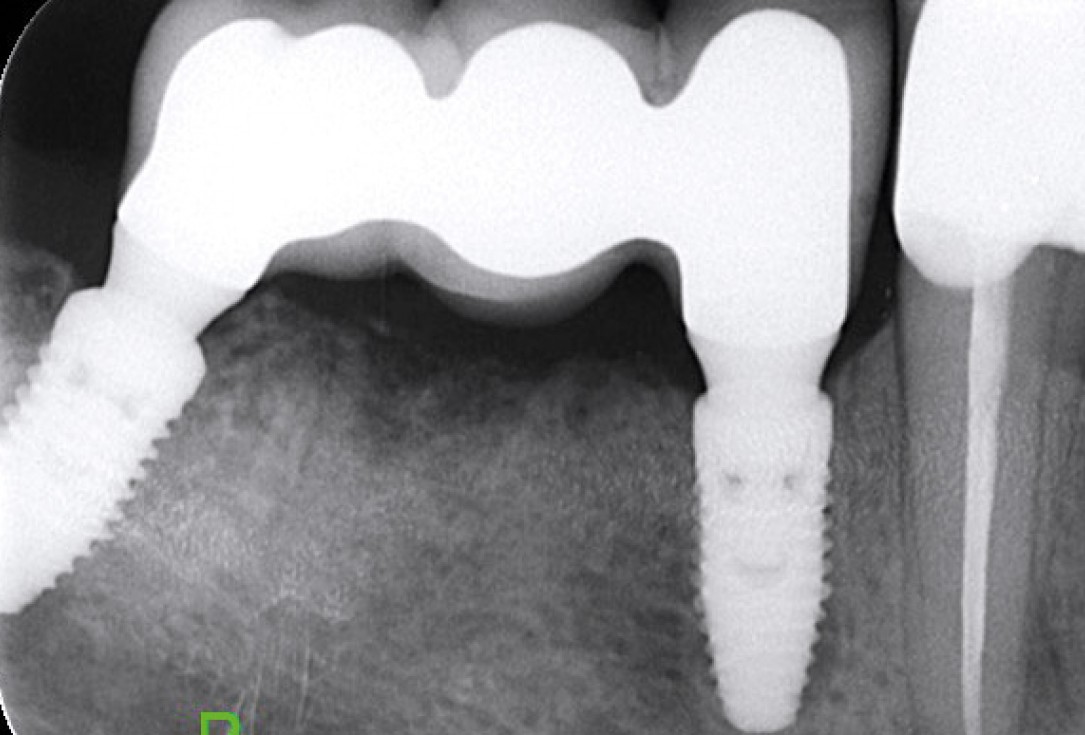

Multiple socket preservation in the mandibular with collacone® max – Dr. D. Jelušić